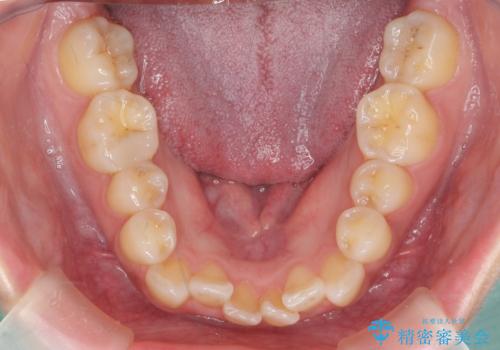

- 前歯のがたつき、受け口を主訴に来院。

上の前歯が二本裏側に入っていました。(反対咬合といいます)

上はワイヤー部分矯正、下はインビザライン(マウスピース)で部分矯正を行いました。

下の前歯を内側に入れる為、一本抜歯しています。

全体矯正で治そうとすると非抜歯ですとだいぶ口元が前に突出するのに加え、下の前歯が入りきらない可能性がありました。上下左右4本抜歯となるため、それを回避するのに下の前歯を1本抜歯して、下の前歯を確実に内側に入れています。